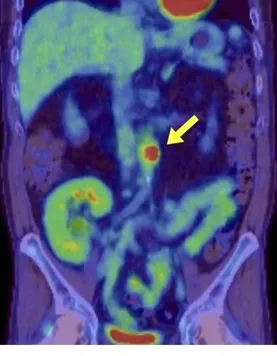

Hipercalcemia em DRC no pós-artroplastia: e se o vilão não for o PTH? Pistas discretas — 1,25(OH)₂D↑, ECA↑ e PET “quente” na prótese — apontam para ASIA por cimento ósseo. Acompanhe o raciocínio que faz o diagnóstico emergir e muda a conduta.

Valkercyo Feitosa